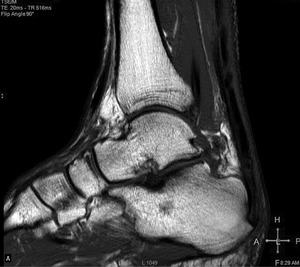

Pacjent, lat 52, zgłosił się do lekarza ortopedy z powodu silnego bólu w okolicy prawej pięty, który wystąpił nagle poprzedniego dnia podczas treningu piłki nożnej. Pacjent uprawia sport regularnie. Do tej pory nie cierpiał z powodu żadnych dolegliwości bólowych tej okolicy, a początek bólu nie był związany z bezpośrednim urazem. Podczas badania stopy okolica ścięgna Achillesa (piętowego) była obrzęknięta i bolesna, ruchy czynne w stawie skokowym znacznie ograniczone. Stwierdzono brak palpacyjnej bolesności w okolicy kostki przyśrodkowej i bocznej z zachowaną stabilnością w ruchach na boki.

Obrzęknięta okolica ścięgna Achillesa wraz z nagłym początkiem dolegliwości wskazuje na jego zerwanie. Niemniej możliwość wykonywania czynnych ruchów w stawie skokowym, nawet w niewielkim zakresie, przemawia za innym rozpoznaniem. Nie występuje też wyczuwalna luka w ścięgnie, jednak może być ona maskowana obrzękiem tej okolicy. Zapalenie kaletki głębokiej ścięgna Achillesa również może wywołać podobne objawy. Często wiąże się ono z występowaniem wyrośli kostnej na kości piętowej (deformacja Haglunda), która drażniąc kaletkę, wywołuje jej stan zapalny. Do złamań zmęczeniowych kości piętowej najczęściej dochodzi u żołnierzy oraz sportowców, którzy biegają długie dystanse po twardym podłożu. Jednakże w tym wypadku jest to mało prawdopodobne rozpoznanie, ponieważ pacjent może stanąć na pięcie oraz nie ma krwiaka i obrzęku tej okolicy.